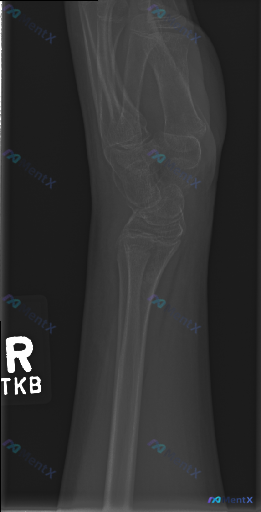

整理到一张影像资料的分析背景,想和大家讨论一下这种情况的临床思路: - 影像检查:右腕侧位X光片 - 关键影像表现: 1. 骨骼系统尚未发育成熟,桡骨远端可见清晰骨骺线(生长板) 2. 各腕骨骨化中心显示,排列整体尚连续,未见明显骨皮质中断或明确骨折线 3. 桡腕关节、中腕关节间隙清晰,对位关系大致...

整理到一份青少年右腕正位X光片的影像资料及相关临床背景,想和大家讨论一下这类情况的判断思路: 基本情况 受检者处于青少年/儿童生长发育期,有明确的手腕外伤史(临床背景补充)。 影像学表现(客观描述) 1. 骨骼发育:桡骨、尺骨远端可见明显骺板(生长板),骨骺尚未完全融合; 2. 骨折/脱位:桡骨远端...